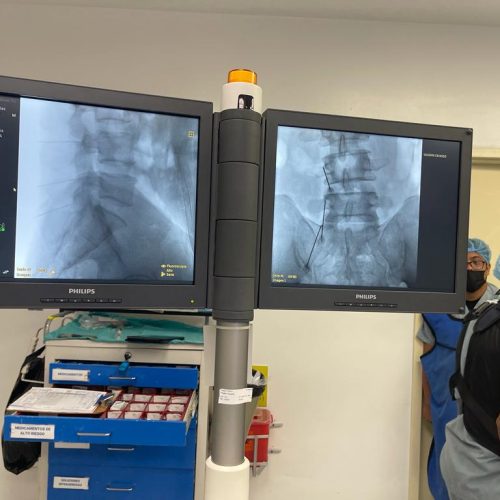

4. Fusión Vertebral (Lumbosacra o Cervical)

¿Qué es?

Cirugía que une dos o más vértebras para estabilizar la columna y aliviar el dolor.

Fusión Vertebral (Cervical o Lumbosacra)

Es un procedimiento quirúrgico que busca estabilizar la columna vertebral uniendo de forma permanente dos o más vértebras. Se utilizan tornillos, barras y, en ocasiones, una caja intersomática con injerto óseo, para que las vértebras se fusionen en una sola unidad sólida.